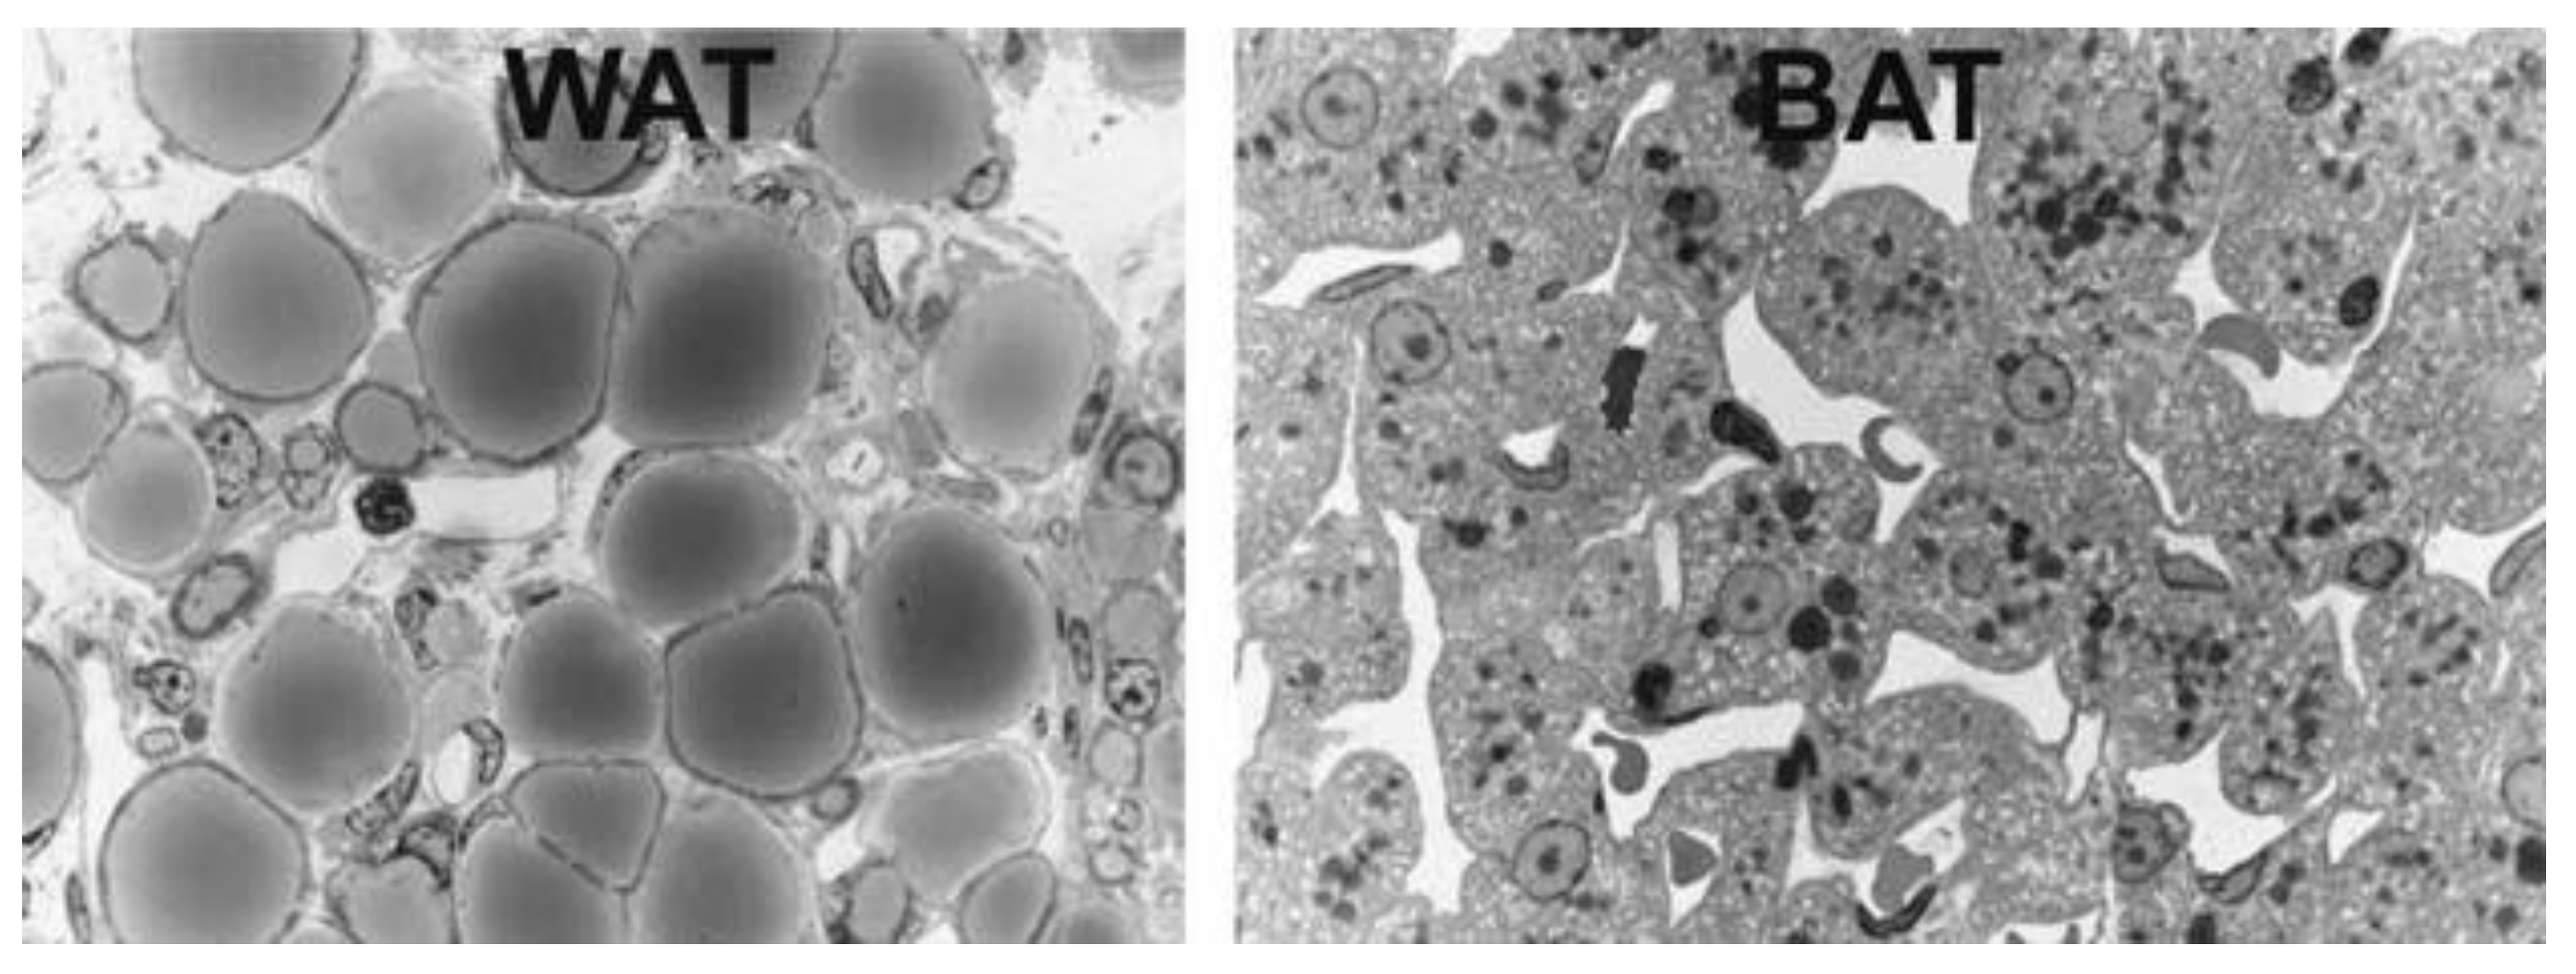

1.1. Adipose Tissue

1.2. Brown, Brite and Beige Adipose Tissue